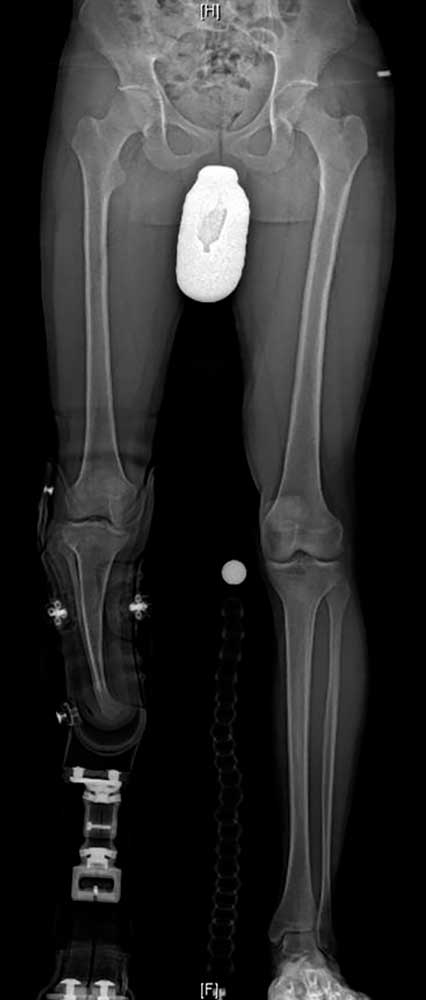

Ein 12-jähriger Patient weist eine Unterschenkel-Dysmelie und eine Varusfehlstellung des Stumpfes auf. Im Alter von 13 Jahren wurden eine Epiphyseodese der proximalen lateralen Tibia und eine Fibula-Epiphyse durchgeführt (Abb. 1a). Nach Wachstumsabschluss zeigt sich weiterhin eine varische Unterschenkelachse, insbesondere im distalen Anteil (Abb. 1b). Die Beinachse kann zwar durch die orthoprothetische Versorgung bzw. den korrekten Aufbau berücksichtigt werden, es entsteht jedoch rezidivierend eine Druckstelle am Stumpfpol sowie lateral an der proximalen Fibula durch mechanische Überbelastung (Abb. 1c). Daraus resultieren massive funktionelle Einschränkungen und letztlich die Indikation zur Stumpfrevision; dadurch kann die mechanische Belastung auf den Stumpf reduziert und gleichzeitig funktionell die Beinachse korrigiert werden.